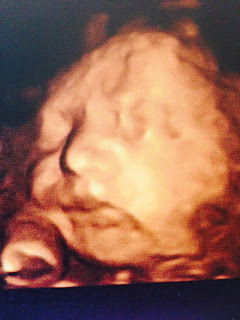

| Eco 20 semanas |

| Eco 26 semanas |